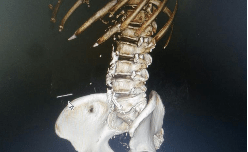

文章图片

三维重建显示阿婆断针的位置 。

确定针的位置后 , 潘裕国主任迅速为梁阿婆安排介入手术 , 通过垂直面向下切开2厘米 , 成功将针从腹中取出 。 此外 , 医院还给梁阿婆打了破伤风针 , 避免感染风险 。 由于针扎的位置就在“包块”处 , 阿婆的感染可能要面临更久的愈合期 。 目前 , 梁阿婆已平安出院 。